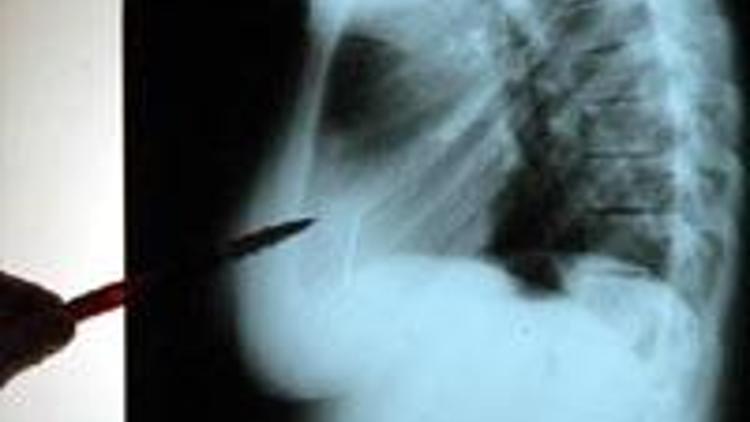

ESKİŞEHİR'de zihinsel engelli 13 yaşındaki S. B.’nin kalbinden 2 dikiş iğnesi çıkartıldı.

Uzun süreden bu yana göğüs ağrısı şikayeti bulunan S. B., yakınları tarafından Eskişehir'deki bir hastaneye götürüldü. Çekilen röntgen filminde kalbinde 2 iğne olduğu belirlenen S. B., Eskişehir'deki Osmangazi Üniversitesi (ESOGÜ) Tıp Fakültesi Hastanesi'ne sevk edildi. S., burada ESOGÜ Tıp Fakültesi Hastanesi Başhekimi ve Kalp Damar Cerrahisi Ana Bilim Dalı öğretim üyesi Prof.Dr. Bülent Tünerir tarafından ameliyata alındı. Endoskopik yöntemle yapılan ameliyatla S.’nın kalbinden 2 adet dikiş iğnesi çıkartıldı.

İğnelerin 13 yaşındaki S. B.'nin küçük yaşlarda kalbine girmiş olduğunu düşündüklerini anlatan Prof.Dr. Bülent Tünerir, 2 iğnenin kalbin içindeki duvara yapışmış ve dokuyla örtülmüş olduğunu kaydetti. Başhekim Prof.Dr. Tünerir, “İğneler oksitlenmiş, yeni değil. Yıllar içinde oksitlendiğini, daha küçük yaşlarda kalbe girmiş olabileceğini düşünüyoruz. İğneler kalbin içindeki duvara yapışmış ve dokuyla örtülmüş” dedi.